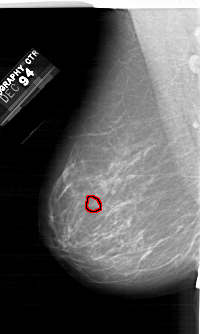

A_1245_1.RIGHT_CC

RIGHT_CC LINES 6271 PIXELS_PER_LINE 3406 BITS_PER_PIXEL 12 RESOLUTION 43.5 NON_OVERLAY

FILE: A_1245_1.LEFT_CC.OVERLAY

TOTAL_ABNORMALITIES 1

ABNORMALITY 1

LESION_TYPE CALCIFICATION TYPE PLEOMORPHIC DISTRIBUTION CLUSTERED

ASSESSMENT 4

SUBTLETY 4

PATHOLOGY MALIGNANT

TOTAL_OUTLINES 1

BOUNDARY